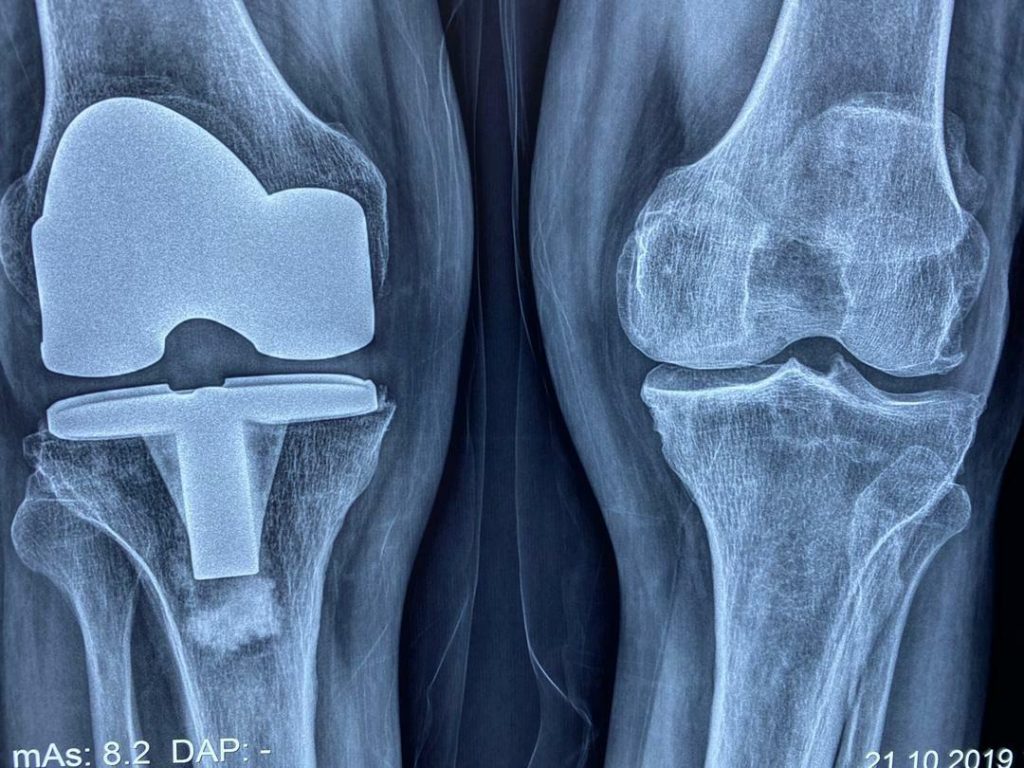

درصورتی که شدت آسیب وارد شده به مفصل به گونه‌ای باشد که با سایر روش‌های درمانی آسیب برطرف نشود، جراح ارتوپد عمل تعویض مفصل را برای درمان توصیه می‌کند. با این عمل، بخشی یا همه محل آسیب دیده مفصل با پروتز جایگزین می‌شود. عمل تعویض مفصل به طرز قابل توجهی درد مفاصل آسیب دیده را کاهش می‌دهد، موجب بهبود توانایی حرکتی مفصل و کاهش مشکلات حرکتی فرد و به طور کلی باعث بهبود کیفیت زندگی فرد می‌شود.

انواع عمل جراحی‌ تعویض مفصل یا آرتروپلاستی، با توجه به نوع مفصل عبارتند از: عمل تعویض مفصل زانو، عمل تعویض مفصل لگن و ران، عمل تعویض مفصل شانه، عمل تعویض مفصل آرنج و عمل تعویض مفصل مچ پا.

• آرتروز یا استئوآرتریت

• ضربه و شکستگی داخل مفصل که بد جوش خورده است یا در رفتگی که بد جا افتاده است یا آسیب رباطی که به خوبی درمان نشده است.